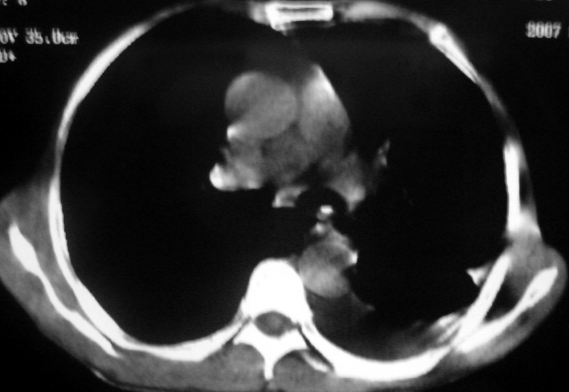

男,54岁,咳嗽,气喘半年,胸痛一月.

血性胸水

左侧胸腔积液 斜裂积液 心包积液 左肺不张 考虑左肺ca并胸膜心包转移。